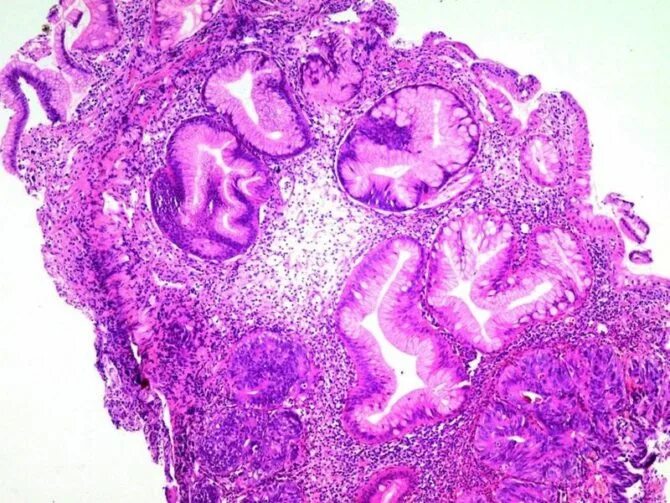

Высокодифференцированная аденокарцинома кишки